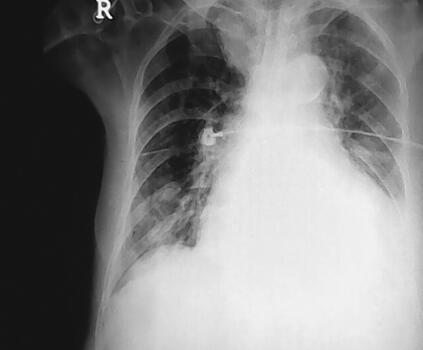

辅助检查:血气分析:pH 7.154,PCO2 38.7mmHg,PO2 88.3mmHg,COHb 27.8%,O2Hb 69.1%;电解质:钠147mmol/L,钾3.6mmol/L;血常规:WBC 18.71×109/L,N 89.24%,Hb 141g/L,PLT 177×109/L;D-二聚体896μg/L;生化指标:BUN 9.1mmol/L,Cr 88μmol/L,CK 178IU/L,CK-MB 14μg/L,Tn-i 1.52μg/L,BNP 14557.7pg/ml。心电图:房颤,ST-T改变;胸片:支气管炎,右下肺及左上肺炎症,右侧胸膜肥厚,心影增大(图1)。

图1 支气管炎,右下肺及左上肺炎症,右侧胸膜肥厚,心影增大